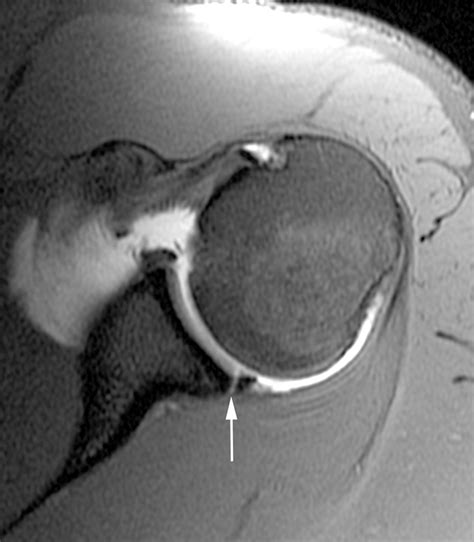

A labrum detachment shoulder injury is frequently categorized by its location. For instance, a SLAP tear (Superior Labrum Anterior to Posterior) involves the top part of the labrum, while a Bankart lesion typically involves the lower front portion, often resulting from a shoulder dislocation. Recognizing the underlying cause is the first step toward effective management.

If you suspect a labrum detachment shoulder injury, seeing an orthopedic specialist is essential. Because labrum tears are soft-tissue injuries, they do not show up on standard X-rays. Instead, doctors rely on more sophisticated diagnostic tools to confirm the extent of the damage.

| MRI Arthrogram | An MRI performed with contrast dye injected into the joint to highlight cartilage tears. |